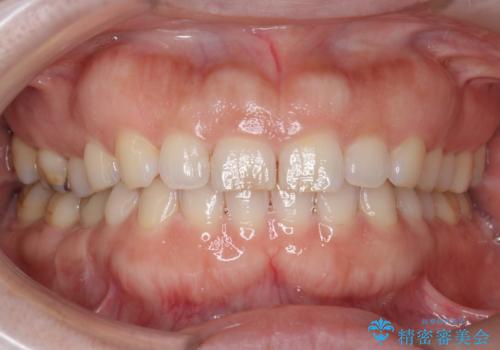

オフィスホワイトニングで、明るく白い歯に!

- ホワイトニングで、ご自身の歯を今より白くしたいと、希望されました。

もともと歯が白めの方でしたので、一番効果がでる医院で行うオフィスホワイトニング(エクセレント)を

おすすめしました。

オフィスホワイトニング(エクセレント) 担当衛生士 進藤

もともと歯は、白めでしたが明るく透明感がでてやってよかったと

喜んでいただけました。